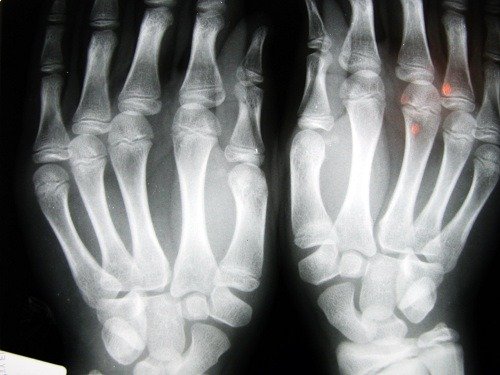

Osteoporoosi on luusairaus, joka aiheuttaa luutiheyden hupenemista. Tälle sairaudelle on ominaista huokoiset luut. Luiden sisäisten solujen kasvaessa kokoa luut muuttuvat hauraiksi ja murtuvat helpommin.

Osteoporoosi on hiljainen, sillä usein se jää huomaamatta kunnes se on jo aiheuttanut vaurioita luuhun.

Murtumia syntyy usein ranteisiin ja myös lannenikamiin. Lannenikamien murtuma on kaikkein vakavin, sillä se vaatii välitöntä leikkausta ja se voi aiheuttaa vakavia seurauksia potilaan terveydelle.